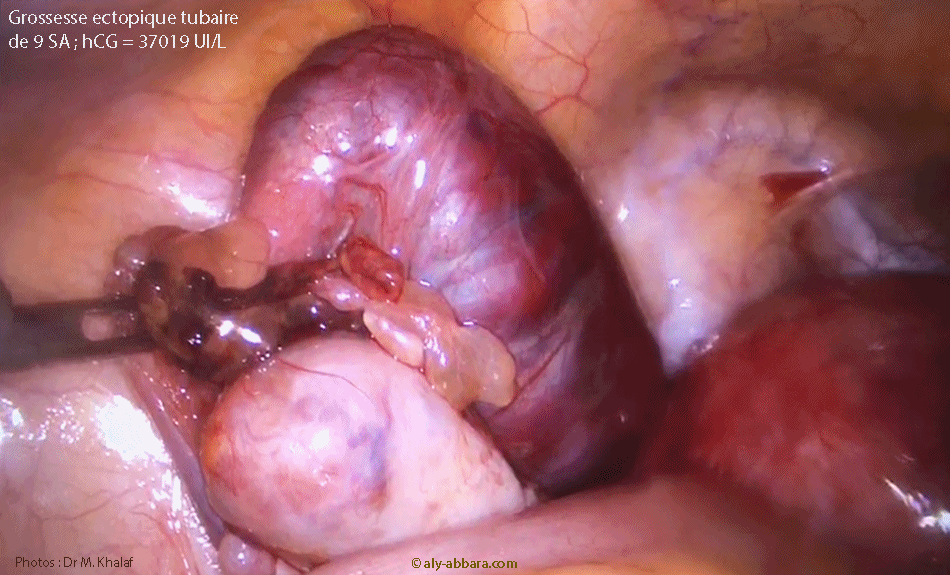

Grossesse extra-utérine tubaire distale évolutive âgée de 9 SA et 2 jours : activité cardiaque positive ; mouvements actifs positifs ; longueur craniocaudale égale à 26,4 mm - coupe transverse de l'utérus

Grossesse extra-utérine tubaire gauche évolutive de 9 SA et 1 J

• Il s'agissait d'une grossesse extra-utérine tubaire gauche en voie de fissuration.

• Cette grossesse ectopique tubaire gauche évolutive est associée à un tableau clinique comportant un retard de règles d'une durée indéterminable par la patiente avec des métrorragies depuis quelques jours, mais aucune douleur spontanée ou provoquée lors l'examen clinique et échographique.

• Biologie : le dosage de β-hCG plasmatique était égal à 37 019 UI/l.

Images  cliniques  suggérées par  Dr M. Khalaf  et prise en charge chirurgicale  par

Dr M. Khalaf et W. El Hajj (Centre Hospitalier de Longjumeau - 91160 - Essonne)